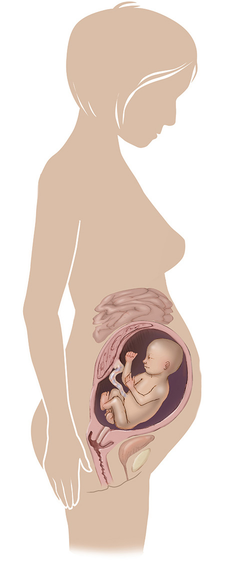

مراحل تطور الجنين أثناء الحمل

تطور الجنين خلال فترة الحمل على ثلاثة مراحل: أول 14 أسبوع من الحمل ، ثم تطوره بداية من الأسبوع 14 وحتى 28 أسبوعا ، ثم الثلث الأخير من 28 إلى 40 أسبوع من الحمل ... المزيد

مراحل تطور الحمل أسبوعيا بالصور

مراحل تطور الحمل أسبوعيا لكل من الأم والجنين داخل الرحم مدعومة بالصور التوضيحية ... المزيد